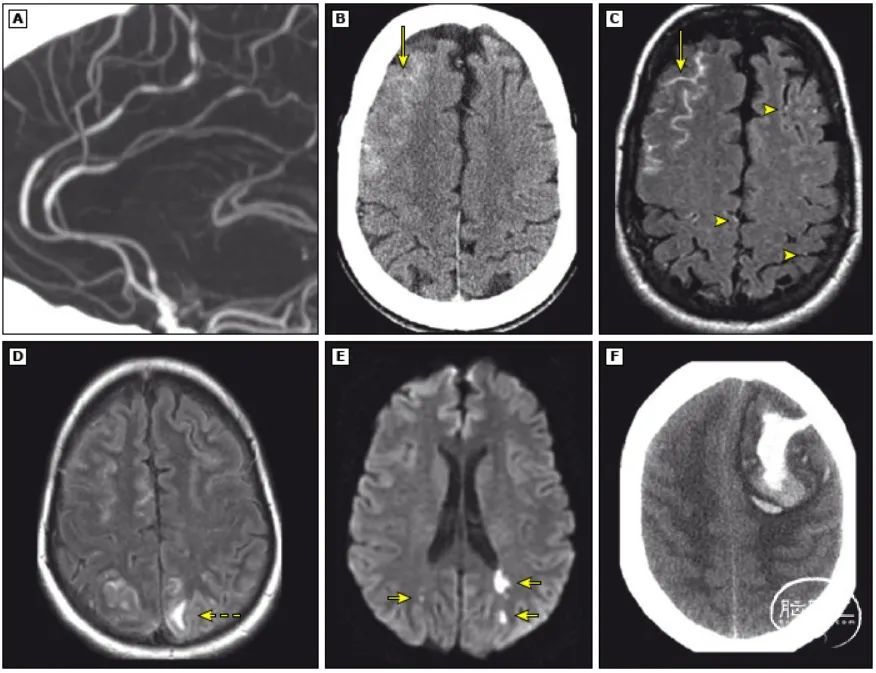

部分患者可出现急性脑梗死、脑水肿、凸面蛛网膜下腔出血、脑叶出血、癫痫发作等脑实质损害的临床表现或体征。这时候,在脑影像学检查上可以看到相应的病变。

图A:脑血管呈串珠样和香肠样狭窄;B:凸面蛛网膜下腔出血;C:凸面蛛网膜下腔出血合并脑沟内点征,这些点征代表扩张的软脑膜血管内缓慢的血流;D:脑水肿;E:急性脑梗死;F:脑出血。

这里需要指出的是,RCVS引起的脑梗死通常呈双侧、对称分布,位于大脑两半球动脉分水岭区或皮质与皮质下交界区,较大的梗死通常呈楔形。这些特征可以和动脉粥样硬化性脑梗死区分。